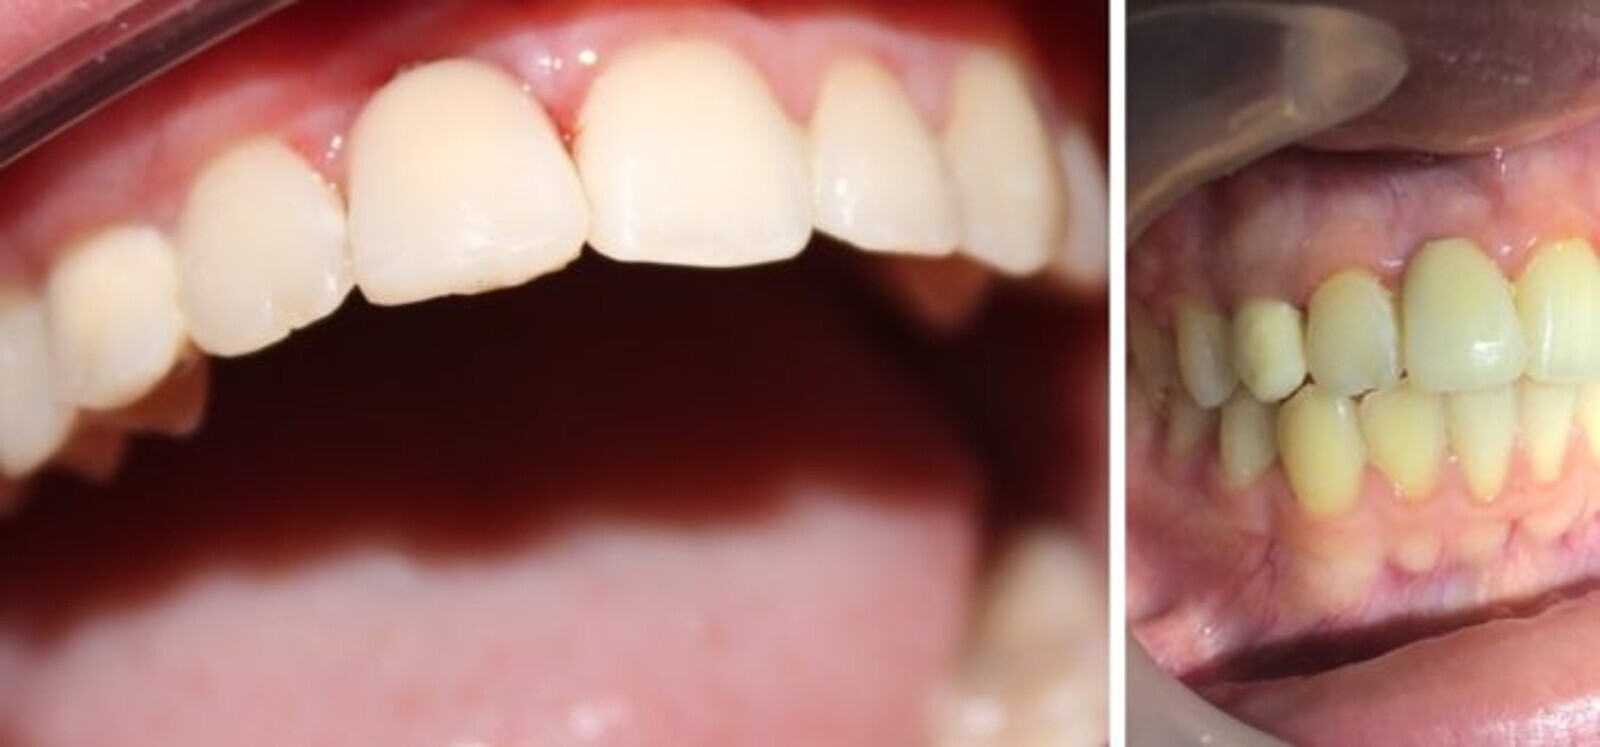

Fig. 12. Imágenes mostrando el estado gingival a 90 y 150 días después de la activación aun con provisorios.

La aplicación de un elemento biocompatible después de un tratamiento de ortodoncia en pacientes con agenesias y/o ausencias, puede mantener el estado de salud gingival para una buena rehabilitación implanto protésica.